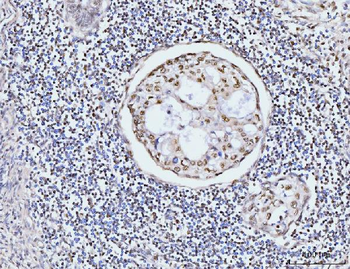

50 μl, 100 μl - MARK3 Recombinant Rabbit Monoclonal Antibody [orb704310]Featured

ICC, IF, IHC-Fr, IHC-P

Human, Mouse

Rat

Rabbit

Recombinant

Unconjugated

50 μl, 100 μl - Featured